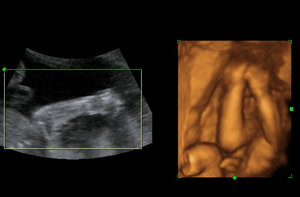

做四维彩超价格?玛丽亚的专家对此表示到,目前,在我院做四维彩超的孕妈妈有很多,因为她们都知道四维彩超可以检查出自己是否怀上畸形儿,而做四维彩超就要选择正规的医院来检查,同时,孕妈妈们对于四维彩超的检查费用也是非常关心的。那么,在哈尔滨做四维彩超需要多少钱呢?

做四维彩超,很多孕妇都会关心检查的费用问题。温馨提醒,由于地区的经济发展水平不同或是医院的收费情况不同,做四维彩超的费用也是不同的。一般来说四维彩超的费用在几百元左右,有的医院费用会略低或者是略高于这个数字,这与医院使用的仪器设备的收费情况不同等方面有关。

专家还指出,如果孕妇在检查的同时还做了其他的检查,那么检查的费用就会整体有所增加,孕妇要是做四维彩超,为了确保检查的准确性比较好的是到正规的医院进行检查。